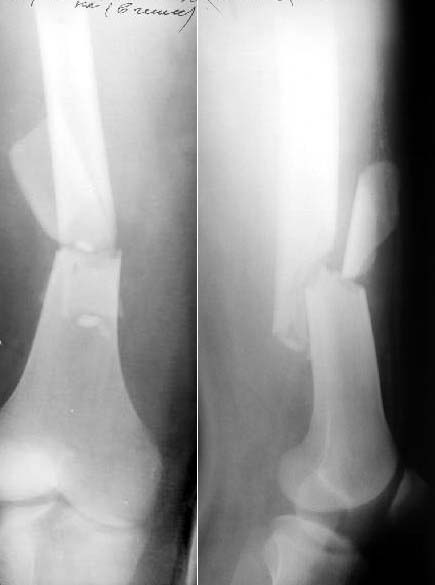

Subject: Femoral fracture with a rotated wedge

A male 19 years old admitted to us after a car accident (was inside) with this femoral fracture (see attachment). As you can see, there is a rotated fragment. The question is whether closed nailing "as is" and early knee function is enough for the case, or open reduction of the fragment should be performed?